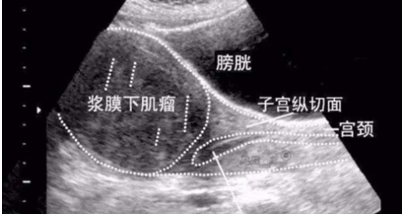

粘膜下肌瘤

还有很多疾病超声显示子宫内膜回声不均,如苗勒氏管混合瘤、内膜损伤性改变(子宫内膜炎,宫腔黏连,瘢痕等)、滋养细胞疾病、间质细胞增生、子宫内膜结核等。